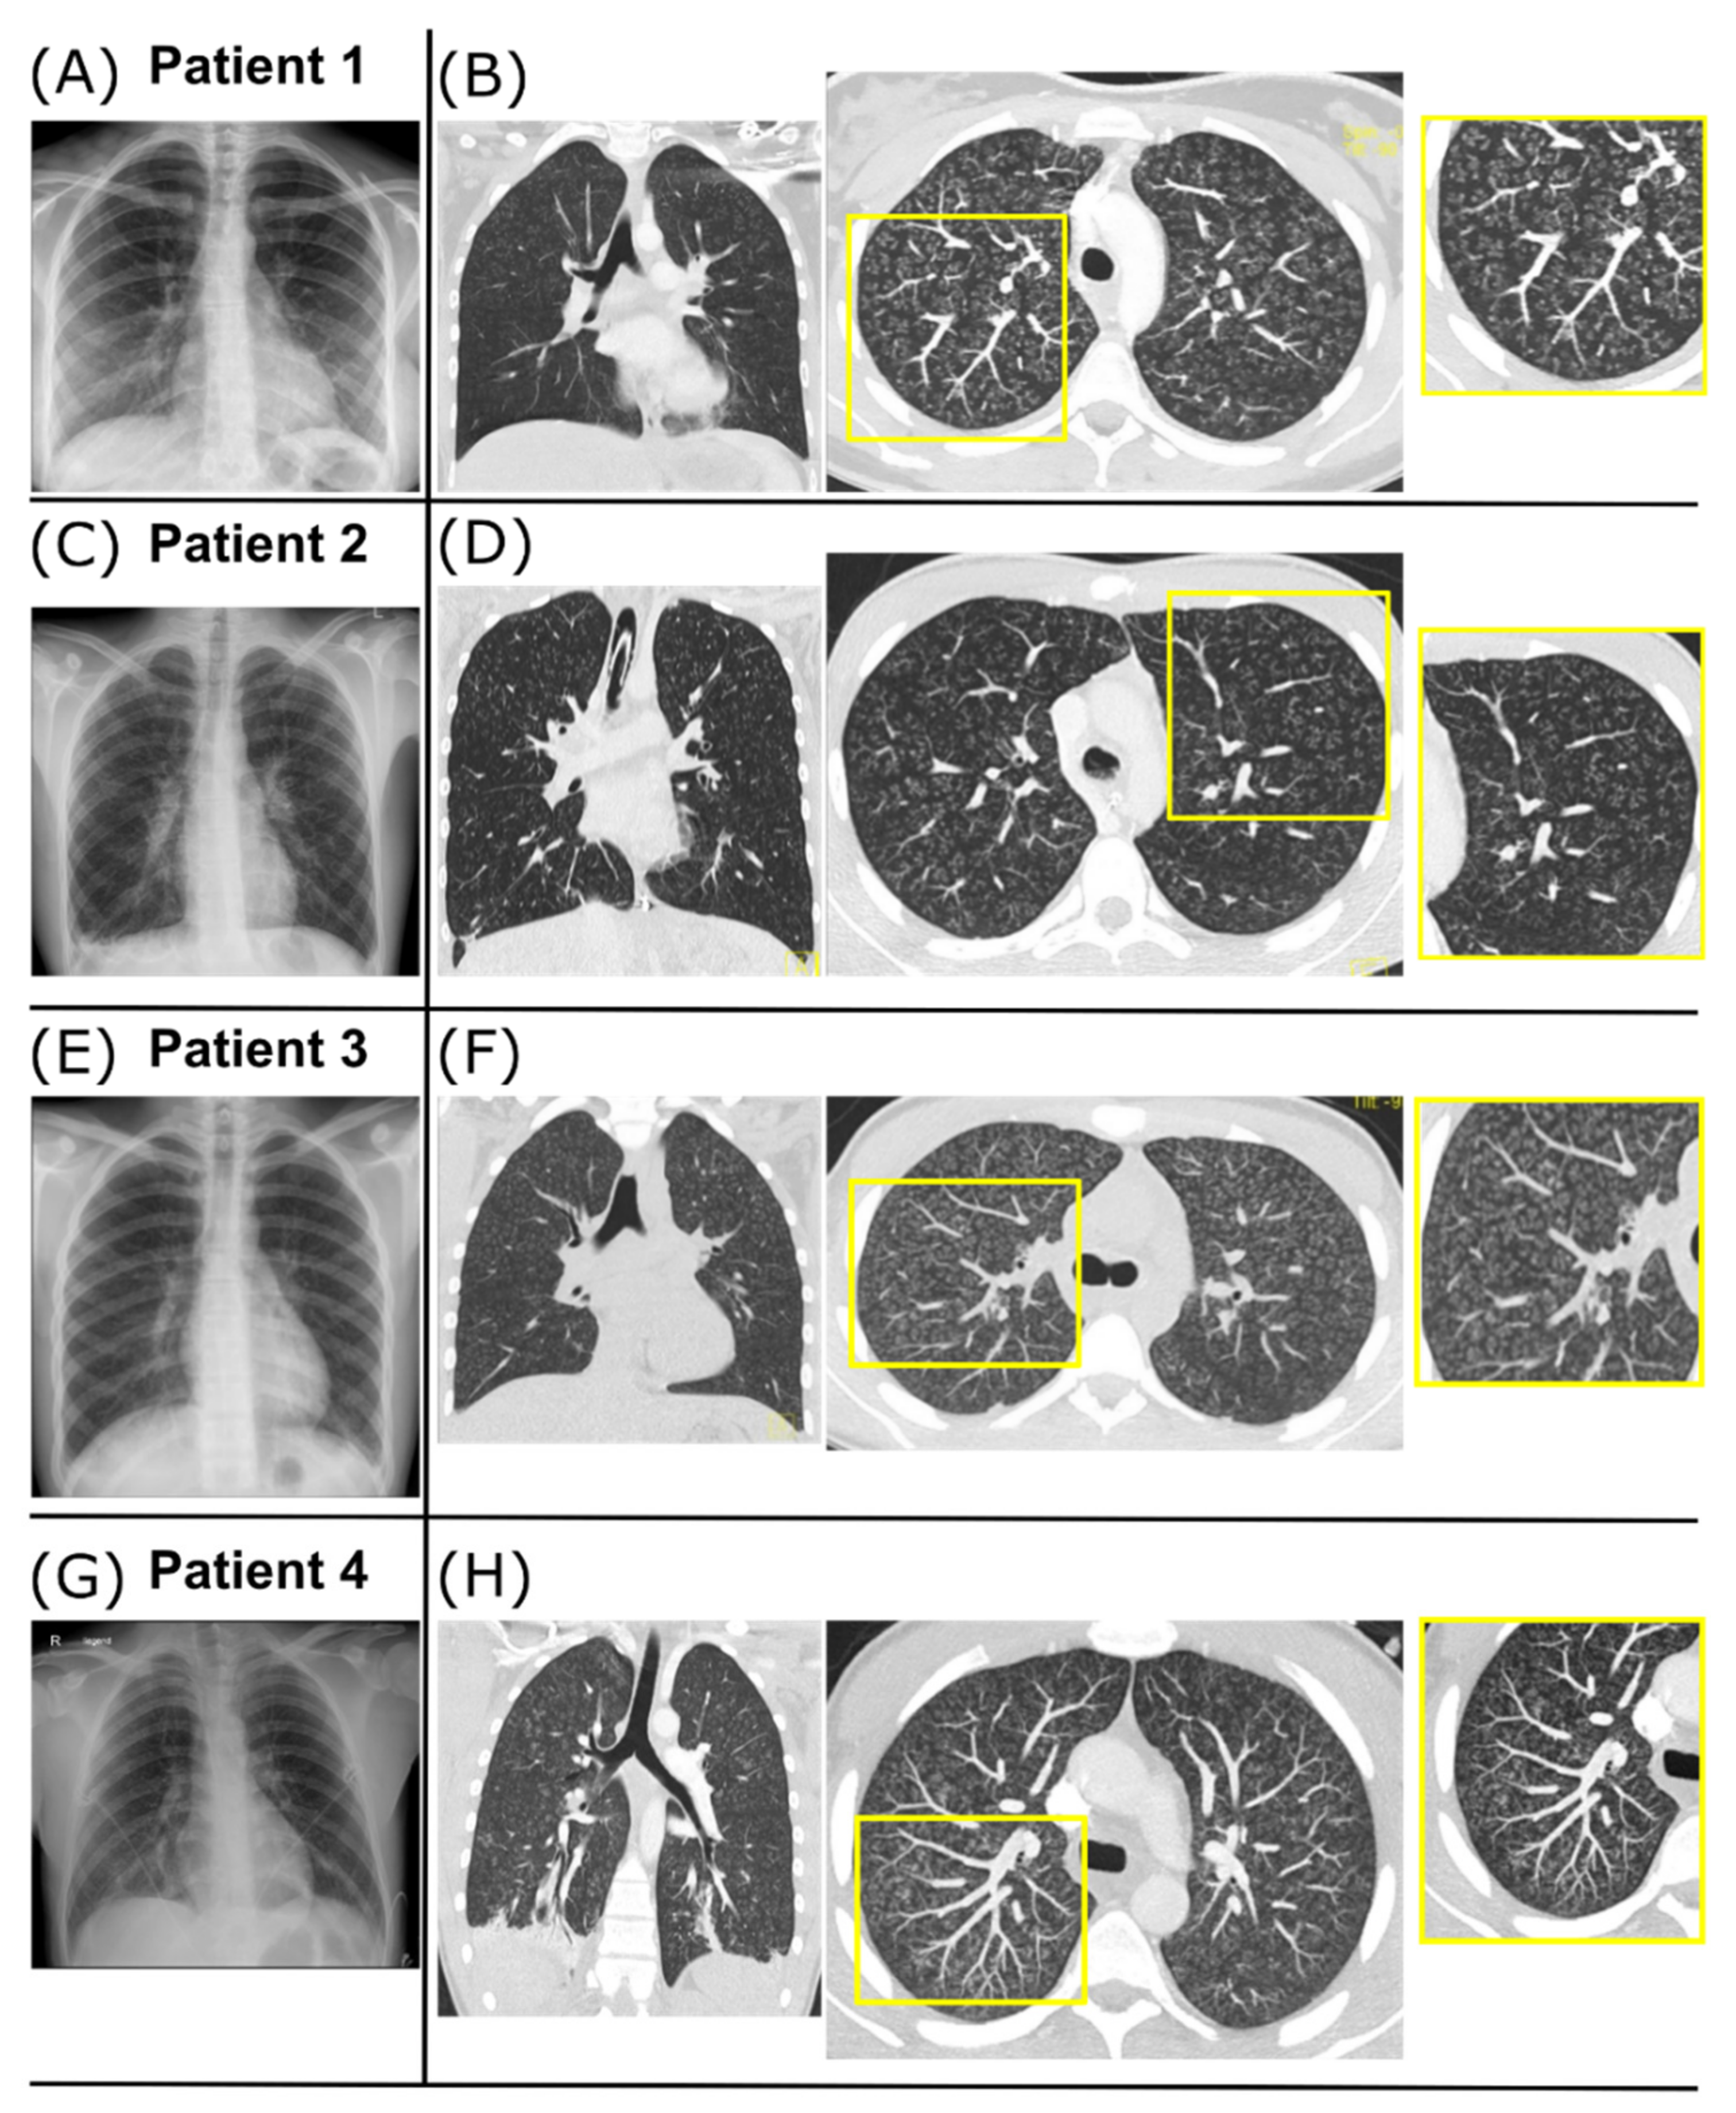

2.1. Case 1

2.2. Case 2

2.3. Case 3

2.4. Case 4